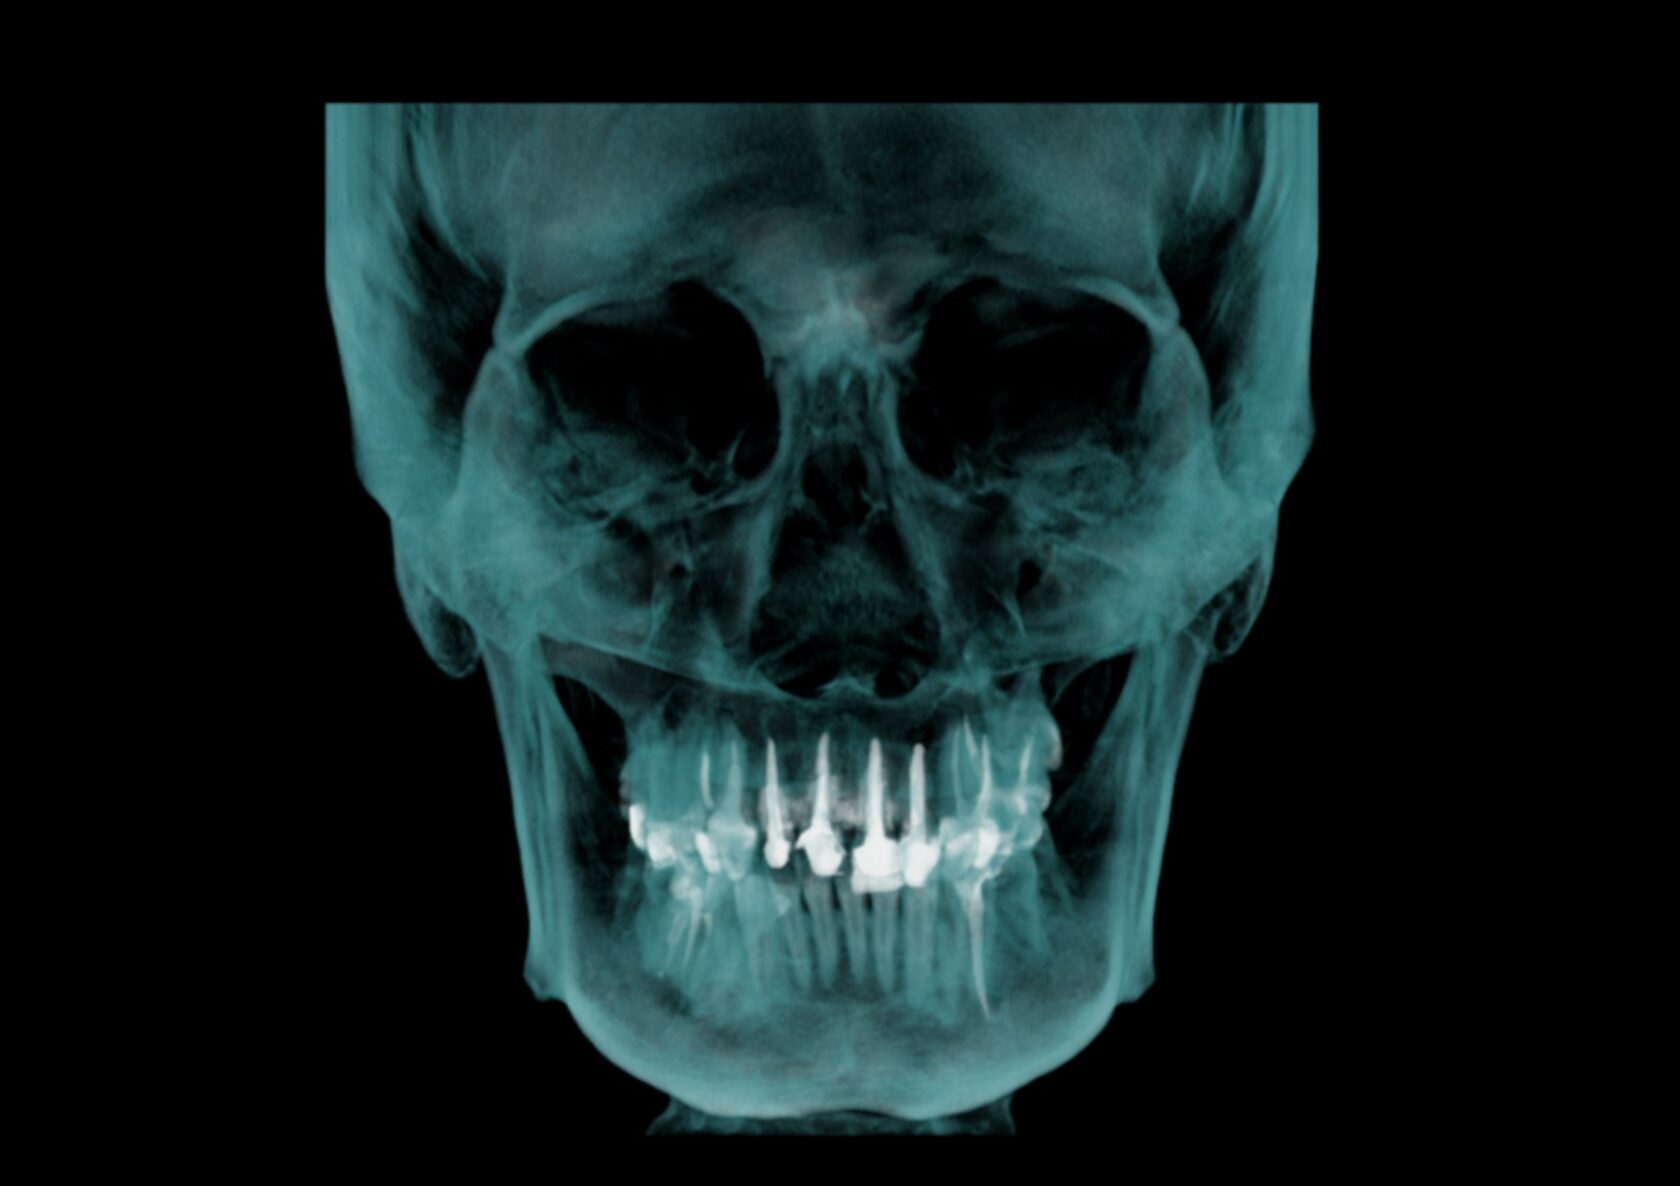

Оценка всего челюстно-лицевого комплекса (лицевого скелета) включая верхнюю и нижнюю челюсти, ВНЧС, дыхательные пути, остиомеатальный комплекс и придаточные пазухи носа, профиль мягких тканей.